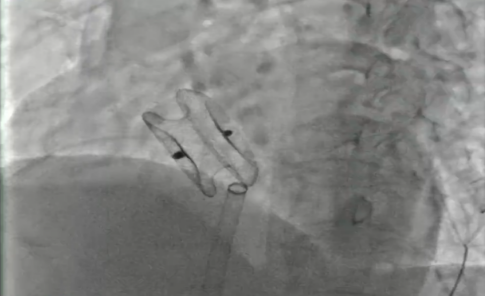

成功封堵

我院心血管內科介入團隊經詳細評估后,開展了充分的術前討論,決定為張阿姨行“室上速射頻消融手術+房間隔缺損封堵術”的一站式手術。該方案通過介入微創實施,一個小穿刺點傷口完成兩個手術,不僅大大減輕分次手術給患者帶來的痛苦及經濟負擔,而且術后恢復快。最終手術成功實施,術后第二天患者即可下床活動。